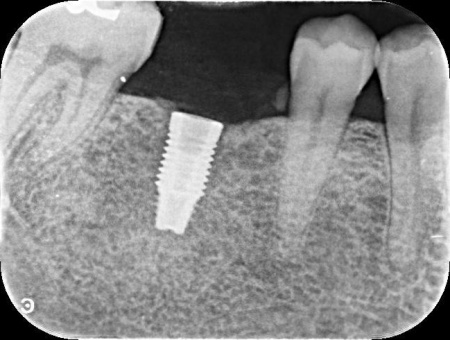

そこで、まずはレントゲンやCTによる検査を実施しました。

その結果、十分な骨の量があり、噛み合わせの歯もインプラントを入れた際に自然に噛める位置に生えていたため、インプラント治療を行う条件は問題ないと判断しました。

①左下奥歯の欠損部位にインプラント埋入手術を実施。インプラントを正しい位置と角度であごの骨に埋入し、傷の治りを待つ